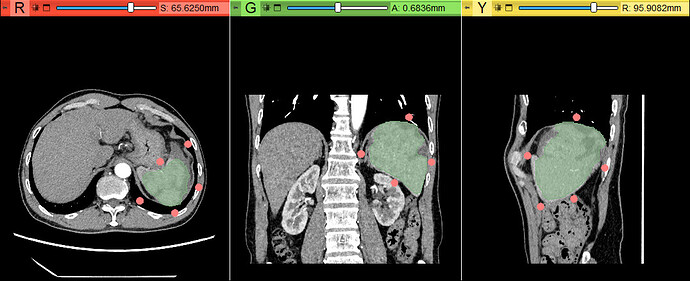

二、Segment from boundary points(DExgtr3D)

首先在Model中选择需要进行分割的组织菜单,再点击基准点,在需要分割的组织周围放置基准点,当放置的基准点足够时,Start由灰色变为彩色,点击后即可自动分割。